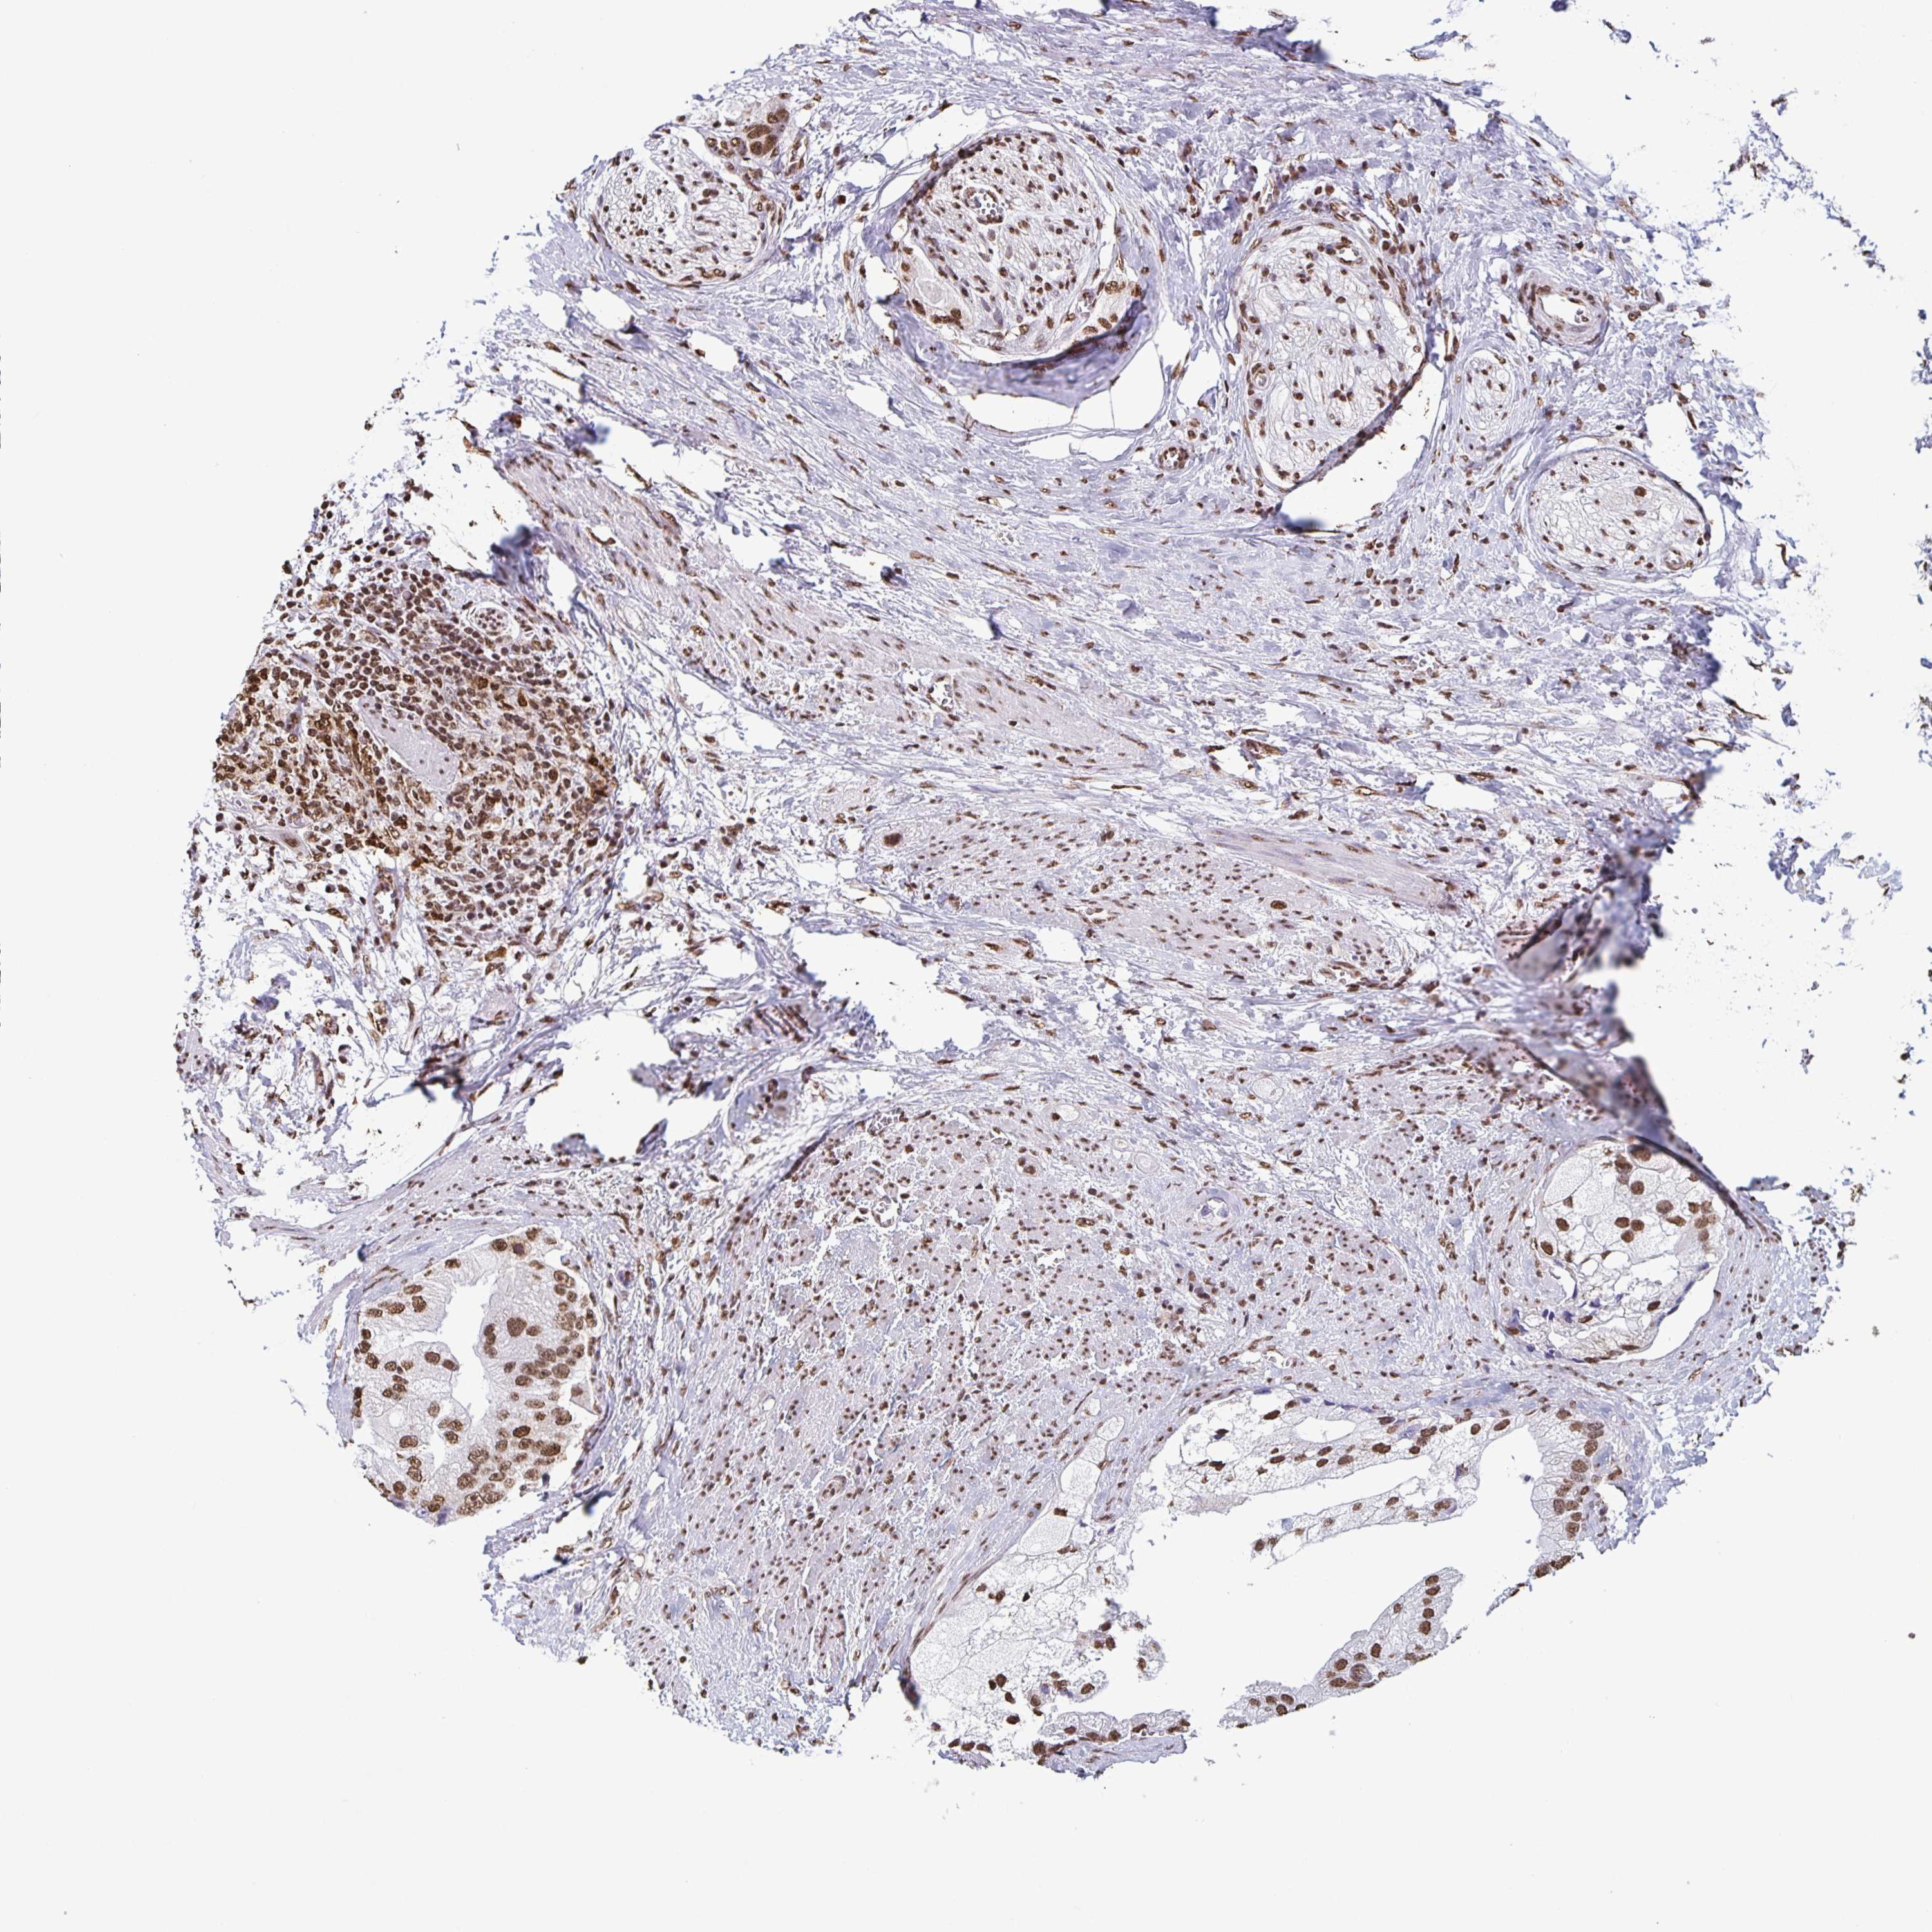

PROSTATE CANCER - Protein expressioni

A mouse-over function shows sample information and annotation data. Click on an image to view it in a full screen mode. Samples can be filtered based on level of antibody staining by selecting one or several of the following categories: high, medium, low and not detected. The assay and annotation is described here.

Note that samples used for immunohistochemistry by the Human Protein Atlas do not correspond to samples in the TCGA dataset.

Antibody stainingi

Antibody staining in the annotated cell types in the current human tissue is reported as not detected, low, medium, or high, based on conventional immunohistochemistry profiling in selected tissues. This score is based on the combination of the staining intensity and fraction of stained cells.

Each image is clickable and will lead to virtual microscopy that enables deeper exploration of all samples and also displays staining intensity scores, fraction scores and subcellular localization as well as patient and tissue information for each sample.

Antibody HPA054422

Antibody HPA060360

Staining

High

Medium

Low

Not detected

Intensity

Strong

Moderate

Weak

Negative

Quantity

>75%

75%-25%

<25%

None

Location

Nuclear

Cytoplasmic/membranous

Cytoplasmic/membranous,nuclear

Adenocarcinoma, High grade

Adenocarcinoma, Low grade